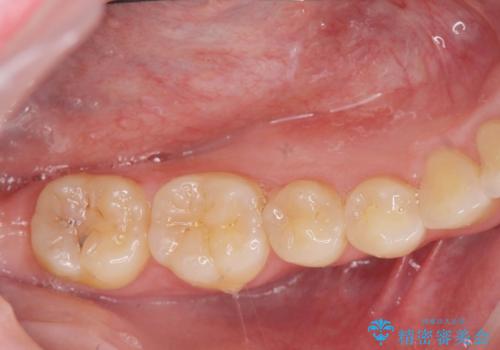

奥の虫歯 ジルコニアクラウンでの修復